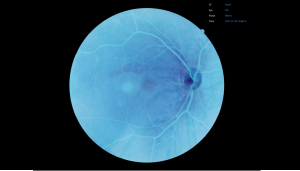

Вбудовані фільтри

FundusVue предоставляет фильтры без красного, негативную пленку, RGB, градации серого, чтобы пользователи могли изменять или применять фотоэффекты к изображению для различных целей.